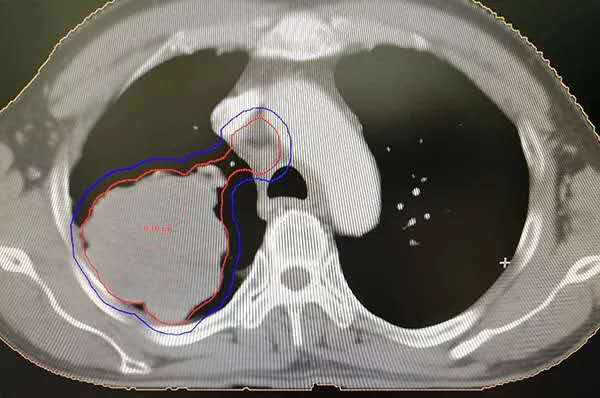

上图为治疗前的肿瘤(红色圈里的为肿瘤,当时肿瘤大小9.3*7.6cm)

东北国际医院放疗科金河天主任带领的团队有着丰富的经验,将李先生收治入科后,第一时间为他制定严谨的放疗计划。因肿瘤在肺部,我科采用容积调强放疗技术,只针对肿瘤部位照射,减小对肿瘤周围其他组织损伤,同时,也大大减少患者治疗后出现放射性肺炎等并发症。